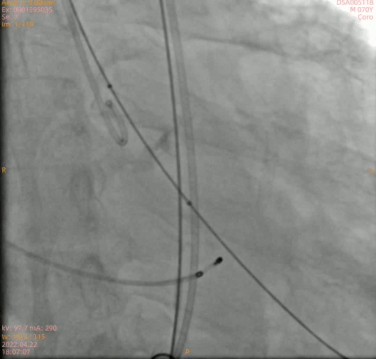

预扩

定位